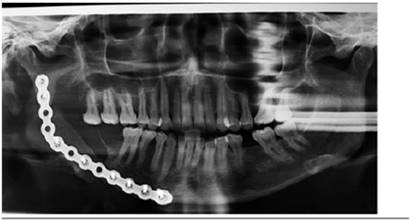

Ocho meses más tarde se retiró el bloque acrílico para realizar el injerto con cresta ilíaca, sirviendo este mismo para la toma del injerto y la consecución de la forma adecuada del mismo (Figura 5).

Actualmente, luego de 12 meses desde la primera cirugía (figuras 6 y 7), la paciente se encuentra en buenas condiciones, sin haber presentado complicaciones durante el tiempo de permanencia del bloque acrílico, con una morfología y dinámica mandibular conservadas, tanto durante el uso del mismo como con posterioridad a éste, en espera de la última intervención en la cual se planifica el retiro de la placa de reconstrucción una vez alcanzada una adecuada integración del injerto al hueso mandibular.